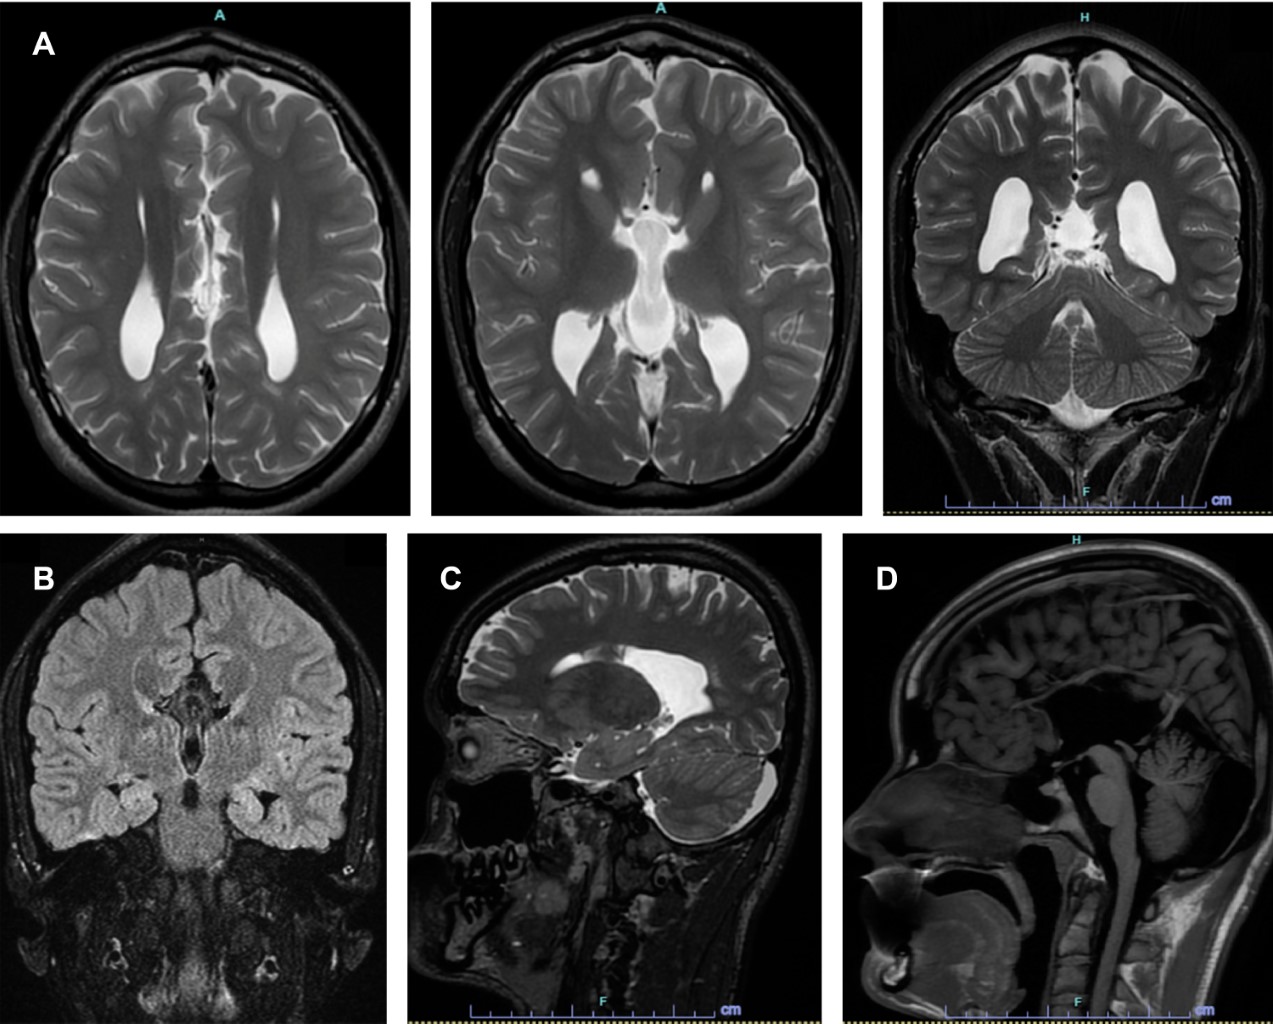

Paciente masculino de 20 años, que acude para valoración médica debido a que presenta crisis convulsivas, por lo cual se le solicitó RM (Figura 1), la cual evidenció los hallazgos de colpocefalia con agenesia del cuerpo calloso.

Figura 1